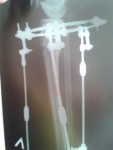

2 месяца с момента операции.

Регенерат растёт хорошо, продолжаем сращение.

Спасибо за совет, Василек! Как на фото ноги мои, ровные со стороны виднее все таки, что- то как -то не пойму какие они получились?!

Привет Adina! Ножки у тебя хорошенькие... Немного иксик есть, но уж лучше так, чем недокрученные. А так они ещё меняться будут с течением времени, так что полностью картинкой ты сможешь насладиться только через несколько месяцев после снятия аппаратов. Как то так...